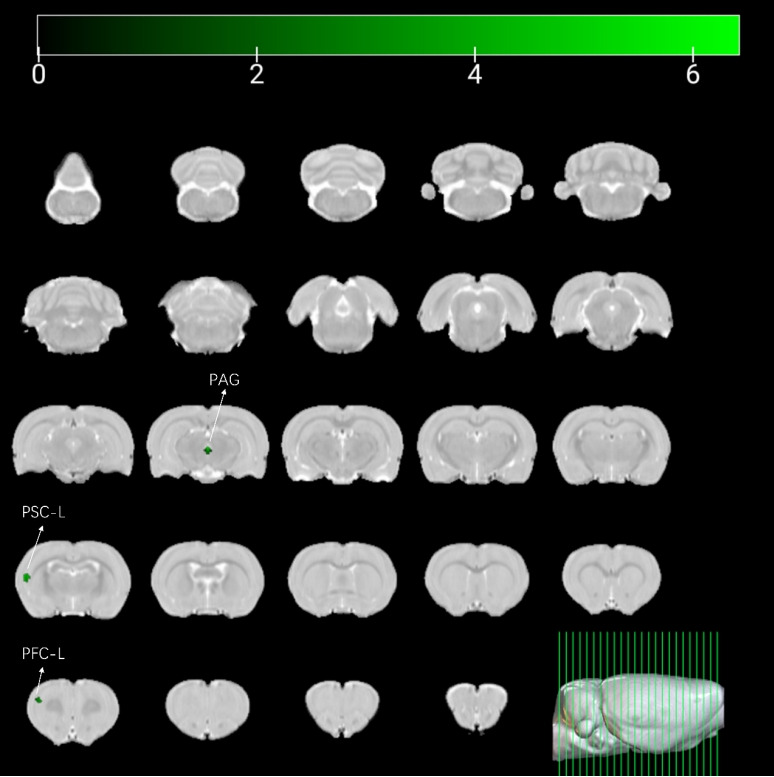

Results: Compared with normal rats, OAB rats exhibited increased ALFF in the left prefrontal cortex, periaqueductal gray (PAG), and left primary somatosensory cortex. In addition, FC between the PAG and pons was enhanced (P=0.002). GLM analysis revealed that the left primary somatosensory cortex, left prefrontal cortex, corpus callosum, left secondary motor area, and right brainstem exhibited decreased activity during SNS (P<0.05). Significant FC changes were observed between several regions: the left cerebellum and left caudal zona incerta (P=0.024), right fasciculus retroflexus and left ventral orbital area (P=0.025), and between the pons and PAG (P=0.004). Seed-to-voxel analysis indicated altered FC between clusters identified in the GLM analysis and regions including the PAG, left cingulate area, left prefrontal cortex, left caudate putamen, and right granular insular cortex.

Conclusion: Our fMRI study identified several alterations in brain activity during SNS in rats. Specifically, activity in the left prefrontal cortex decreased during SNS, and FC between the PAG and pons was reduced. These changes may represent central mechanisms underlying sacral neuromodulation in OAB patients.